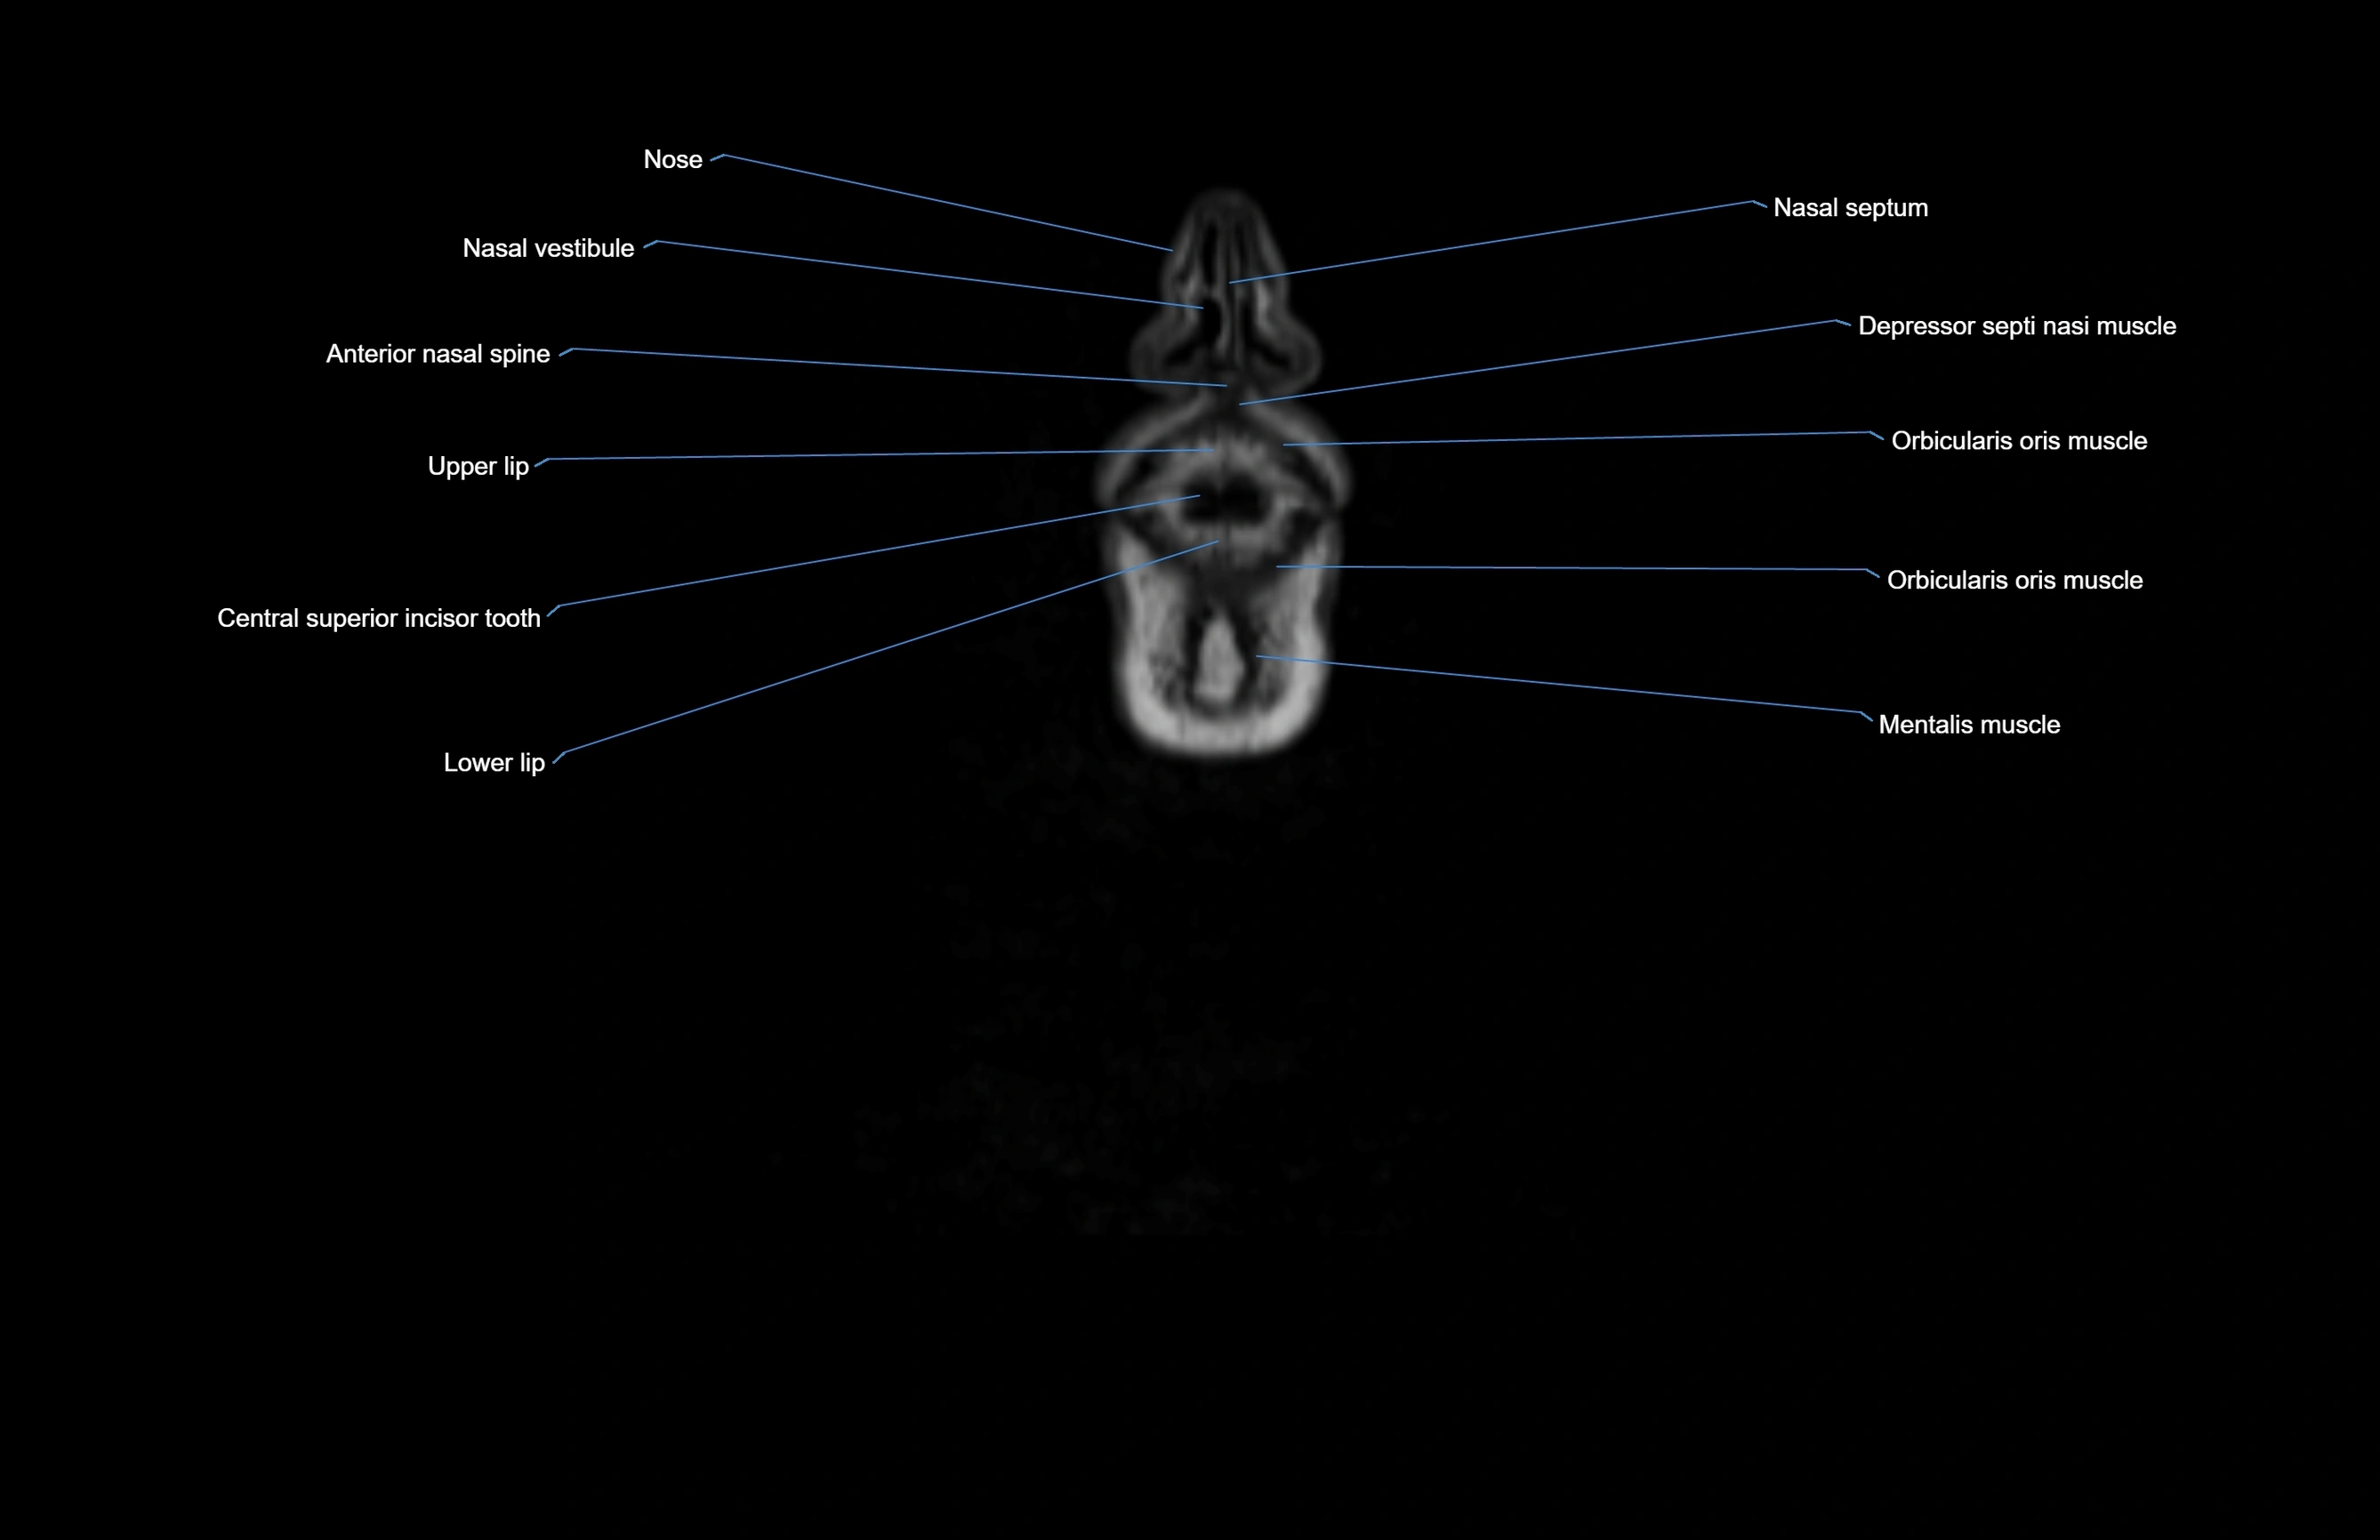

- Anterior nasal spine

- Central superior incisor tooth

- Depressor septi nasi muscle

- Lower lip

- Mentalis muscle

- Orbicularis oris muscle